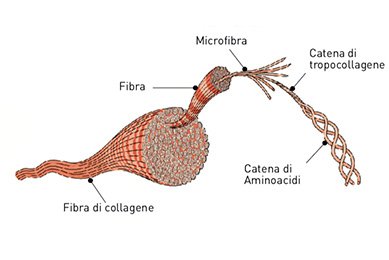

Il collagene ha una struttura fibrosa, che apporta notevole resistenza e flessibilità ai tessuti, e ha una composizione che lo rende unico per l’elevato livello di aminoacidi glicina e prolina, e per le forme idrossilate di prolina e lisina, che non si trovano in nessun altro tipo di proteina.

La sua macromolecola, che ha un peso molecolare (PM) di 300.000 Daltons (Da), è formata da tre catene polipeptidiche di 1000 aminoacidi (AA) ciascuna, che si intrecciano formando una tripla elica.

Le eliche si uniscono tramite i loro estremi costituendo una catena più lunga (tropocollagene) e queste catene si raggruppano poi in parallelo per formare le microfibre, che si uniscono formando le fibre che danno poi origine a quelle di collagene. Questo cordone proteico spesso ma flessibile forma la matrice (rete tridimensionale o fasci di fibre) che costituisce la struttura del collagene.